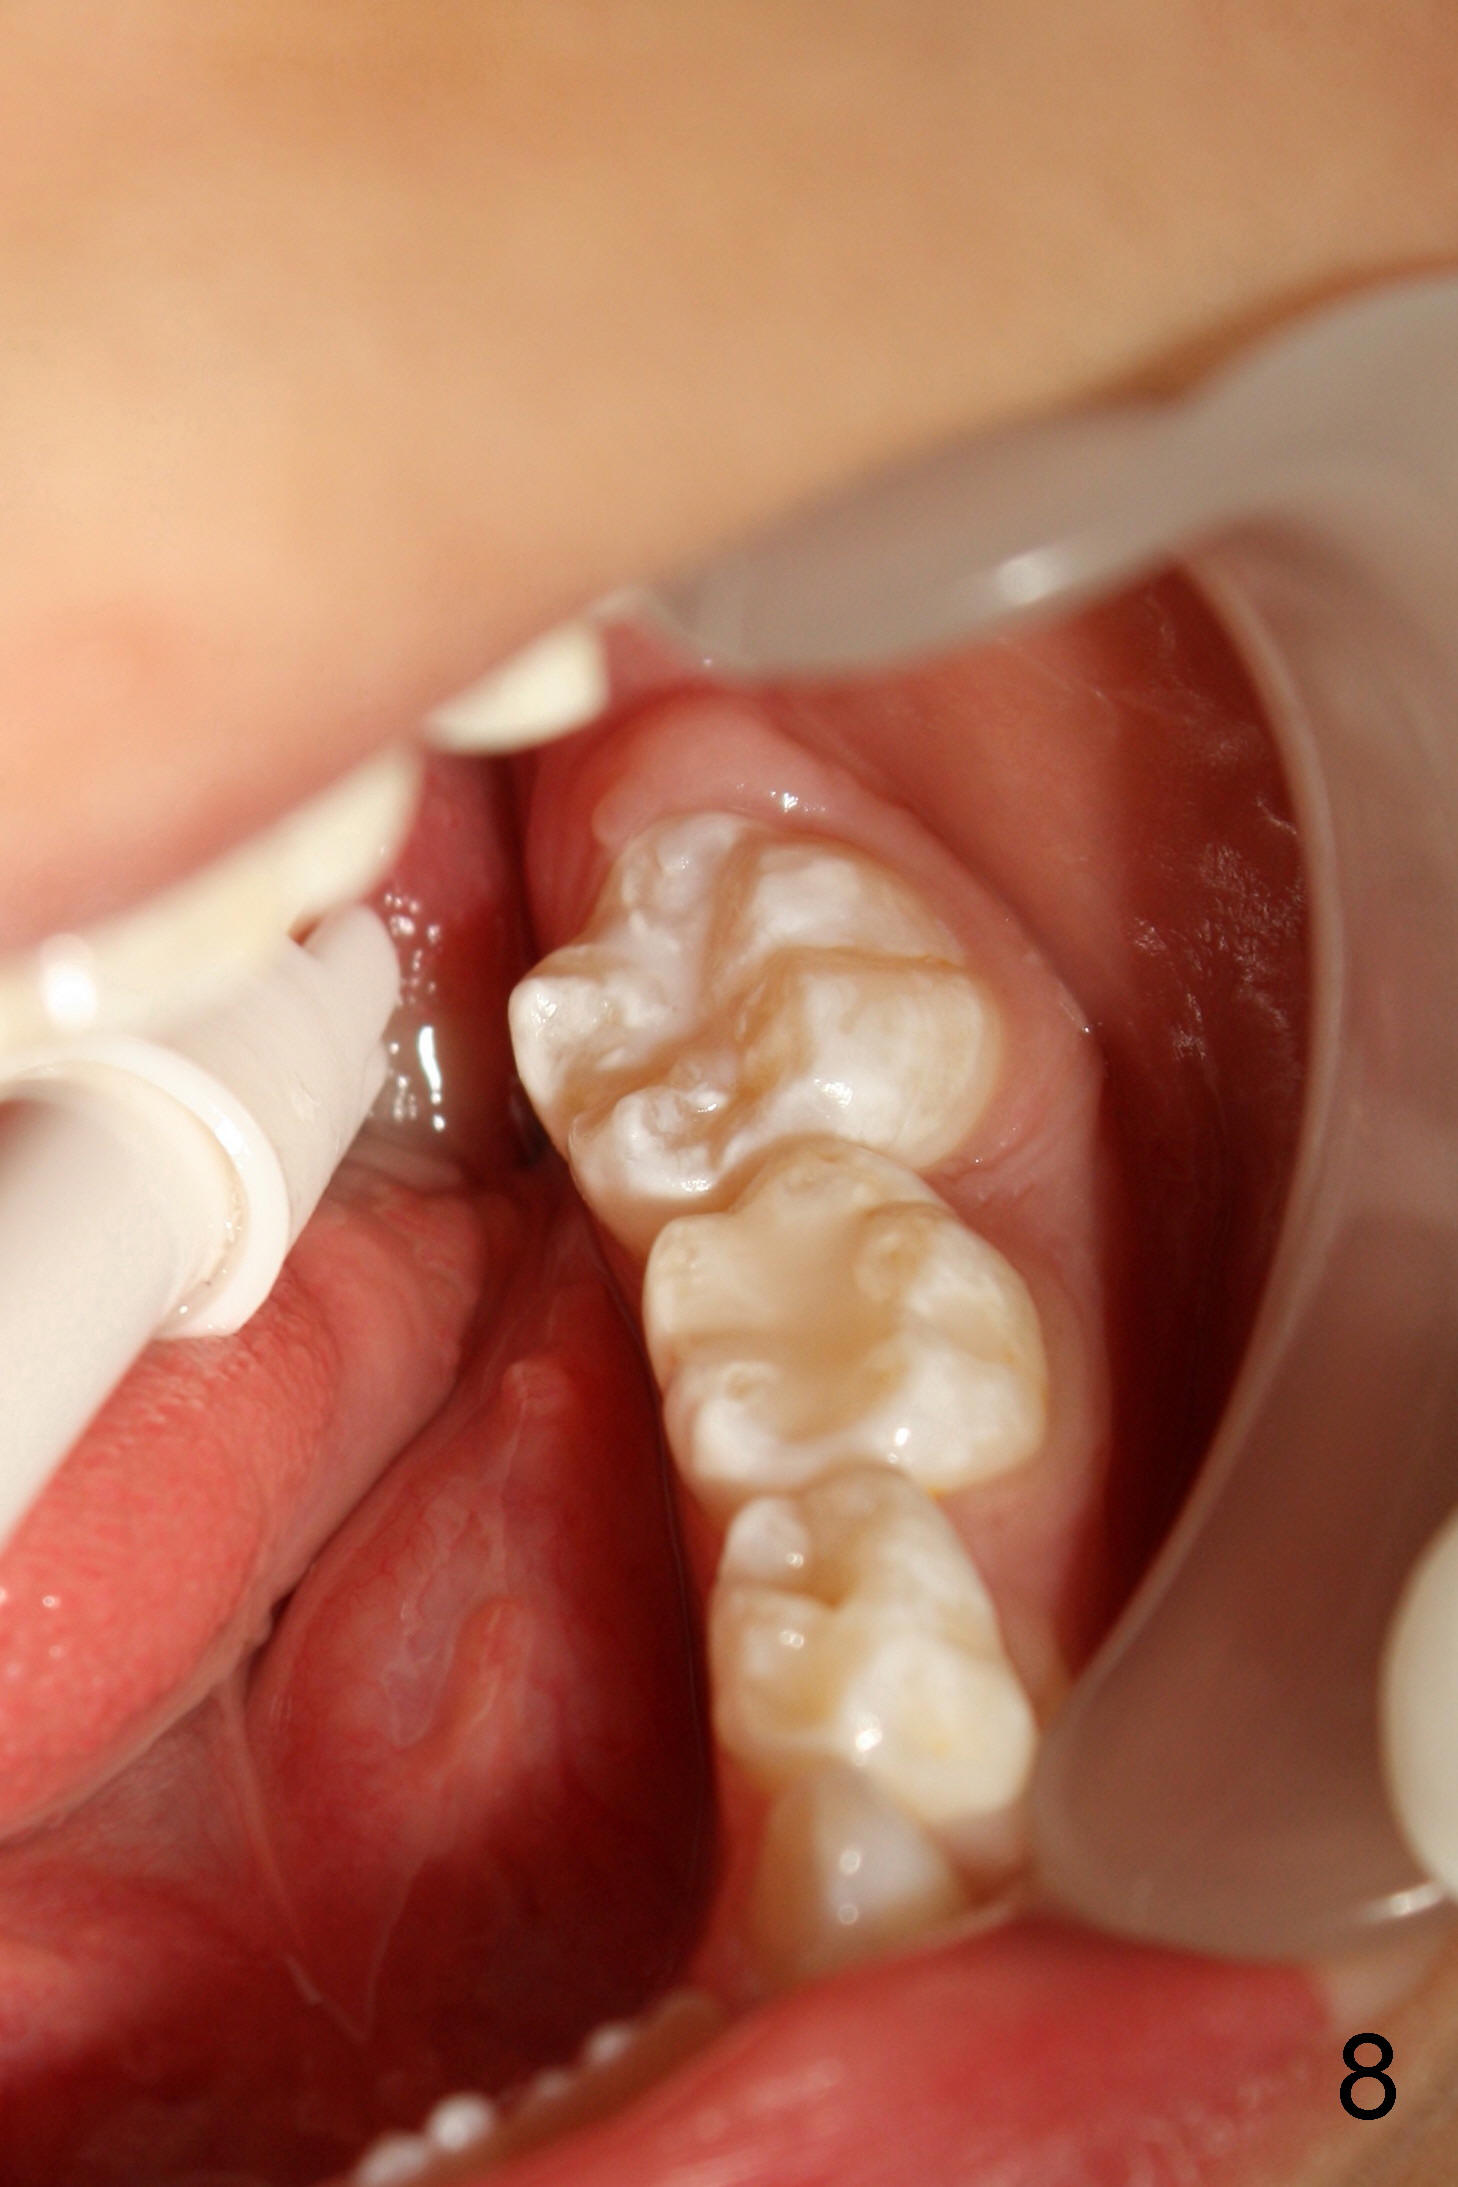

When Devon is 5 years old, there are no spaces between the deciduous teeth (Fig.4-6). The developing upper central incisors are deviated from the midline and off angle (Fig.4: black lines, as compared to Fig.1). Two upper deciduous lateral incisors are in cross bite (Fig.6). LR6 (lower right permanent first molar) rotates (Fig.7 *, as compared to normal LL6 in Fig.8).

当Devon五岁时,没有乳牙间隙(图四至图六),正在发育的恒中切牙不仅远离中线,而且角度不对(图四:斜线,与图一:8,9(恒中切牙)比较)。乳侧切牙反合(图六:D, G)。右下第一恒磨牙扭转(图七:*,与图八:左下相应牙齿对比)。